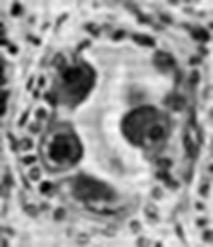

. Малюнок - Герпес-вірусів: А -

нуклеокапсид вірусної частки та відходяча на різну відстань від нього оболонка

формує характерну картину «смаженого яйця»; Б - модель вірусної частки

. Електронні мікрофотографії нуклеокапсидів і віріонів HSV. «А, Б» - негативно забарвлені препарати. «В, Г» - тонкі зрізи заражених клітин. А. 1 - інтактний віріон, непроникне ний для негативної фарби, 2 - капсид. Б. Нуклеокапсид: видна характерна для герпес-вірусів капсомірна структура. В. Віріони з пошкодженими оболонками, що дозволяють бачити електроннощільний тегумент, розташований між поверхнею капсиду і внутрішньою стороною оболонки. Г. Дві частинки з різною орієнтацією тороїдальної серцевини. У разі вібріона 1 зріз зроблено через тороїд перпендикулярно осі симетрії; у разі вібріона 2 зріз зроблений паралельно цій осі.